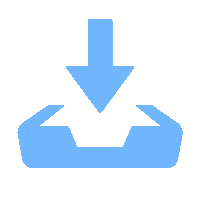

目的 探究肺部超声评分(LUS)、膈肌超声联合常规指标预测小儿重症肺炎(SP)并发急性呼吸窘迫综合征(ARDS)的价值。 方法 选取2022年8月至2023年8月昆明市儿童医院SP患儿160例,均行肺部超声、膈肌超声检查获取LUS、膈肌超声参数[膈肌移动度(DM)、膈肌厚度变化率(TF)],根据SP患儿住院期间是否并发ARDS分为ARDS组67例和非ARDS组93例,比较两组入院时一般资料、血清炎症因子水平、LUS、膈肌超声参数,分析SP患儿并发ARDS的影响因素,并分析LUS、膈肌超声参数预测SP患儿并发ARDS的价值。 结果 SP患儿住院期间ARDS发生率为41.88%(67/160);ARDS组入院时APS、APACHEⅡ评分、血清C反应蛋白(CRP)、白介素-6(IL-6)、高迁移率族蛋白B1(HMGB1)水平、LUS、DM高于非ARDS组,TF低于非ARDS组(P < 0.05);入院时APS、APACHEⅡ评分及血清CRP、IL-6、HMGB1水平、LUS、DM、TF均为SP患儿并发ARDS的影响因素(P < 0.05);LUS、DM、TF预测ARDS的曲线下面积(AUC)分别为0.718、0.742、0.720;常规预测方案(入院时APS、APACHEⅡ评分及血清CRP、IL-6、HMGB1水平联合)的AUC为0.852,新预测方案(常规预测方案基础上联合LUS、DM、TF)的AUC为0.930,新预测方案的AUC明显大于常规预测方案的AUC(P < 0.05)。 结论 LUS、膈肌超声参数DM、TF与SP患儿并发ARDS显著相关,联合常规指标可为临床预测SP患儿并发ARDS提供可靠依据。 Abstract:Objective To explore the value of lung ultrasound score (LUS) and diaphragm ultrasound combined with routine indicators in predicting the occurrence of acute respiratory distress syndrome (ARDS) in children with severe pneumonia (SP). Methods A total of 160 patients with SP were selected from Kunming Children’s Hospital from August 2022 to August 2023, all of whom underwent lung ultrasound and diaphragm ultrasound examination to obtain LUS and diaphragm ultrasound parameters [diaphragm mobility (DM), diaphragm thickness change rate (TF)]. The patients with SP were divided into ARDS group and non-ARDS group according to whether they were complicated with ARDS during hospitalization. The general data, serum inflammatory factor levels, LUS and diaphragm ultrasound parameters were compared between the two groups at admission, and the influencing factors of ARDS in children with SP were analyzed, and the value of LUS and diaphragm ultrasound parameters in predicting ARDS in children with SP was analyzed. Results The incidence of ARDS in SP patients was 41.88% (67/160). APS, APACHEⅡ scores, serum C-reactive protein (CRP), interleukin-6 (IL-6), high mobility group protein B1 (HMGB1) levels, LUS and DM in ARDS group were higher than those in non-ARDS group, TF were lower than those in non-ARDS group (P < 0.05). APS, APACHEⅡ scores, serum CRP, IL-6, HMGB1 levels, LUS, DM, TF were the influencing factors of ARDS in SP children at admission (P < 0.05). The area under the curve (AUC) of LUS, DM and TF predicted ARDS were 0.718, 0.742 and 0.720, respectively. The AUC of the conventional prediction scheme (APS, APACHEⅡ score combined with serum CRP, IL-6 and HMGB1 levels at admission) was 0.852, while that of the new prediction scheme (combined with LUS, DM and TF based on the conventional prediction scheme) was 0.930. The AUC of the new prediction scheme was significantly higher than that of the conventional prediction scheme (P < 0.05). Conclusion LUS, DM, TF, and SP parameters of the diaphragm are significantly correlated with ARDS in children with SP, and the combination of routine indicators can provide reliable evidence for clinical prediction of ARDS in children with SP. -

组别 n LUS(分) DM(cm) TF(%) ARDS组 67 20.15±3.26 1.41±0.34 37.24±3.65 非ARDS组 93 17.48±2.51 1.12±0.28 41.08±4.13 t 5.852 5.905 6.087 P <0.001* <0.001* <0.001* *P < 0.05。 表 3 SP患儿并发ARDS的影响因素分析